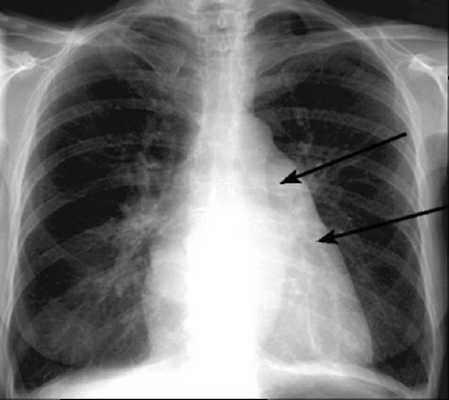

Рентгенологически перегруженный правый желудочек виден расширением контуров справа вверху